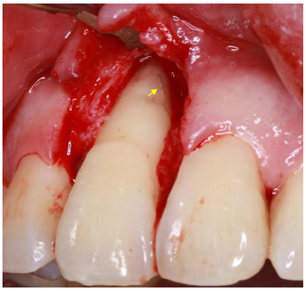

初诊4周后复查(2017年11月8日):检查:11舌侧暂封在,叩痛(-),Ⅰ度松动,唇侧牙周袋仍溢脓。处置:11拟翻瓣探查,翻瓣后11唇侧及近中见大量肉芽,刮治后11近中唇侧根中部见隐裂(图3),快机裂钻磨除隐裂(图4A),填MTA(图4B),填充骨粉后缝合(图5A),上牙周塞治剂(图5B)。

患者初次就诊临床检查11唇侧近中可及深窄牙周袋,x线片11近中牙槽骨角型吸收达根尖就考虑该牙是否存在根裂,因为大多数根纵折的一侧均会有深及根尖部的狭窄牙周袋[3]。x线片根纵裂的特点是有沿牙长轴的牙槽骨吸收,呈现沿根尖至根侧的"J"型骨吸收表现、日晕状或角形吸收[1]。但x线片及CBCT均未见明确根折根裂影像,且开髓后根管长度测量仪能正常侧量工作长度,故而首诊未行手术探查,仅行根管治疗封氢氧化钙及龈下刮治。患者封药2周、4周复查11深窄牙周袋无改善,仍溢脓,根据以往经验,如牙根无缺陷,行标准的根管治疗封药2-4周基本牙龈症状均会消除,故而此时我们决定翻瓣手术探查。翻瓣刮除大量肉芽后于11根中部见隐裂,明确了诊断。